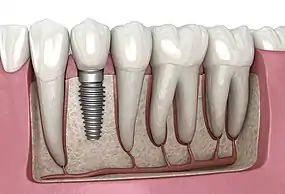

A dental implant (also known as an endosseous implant or fixture) is a prosthesis that interfaces with the bone of the jaw or skull to support a dental prosthesis such as a crown, bridge, denture, or facial prosthesis or to act as an orthodontic anchor. The basis for modern dental implants is a biological process called osseointegration, in which materials such as titanium or zirconia form an intimate bond to the bone. The implant fixture is first placed so that it is likely to osseointegrate, then a dental prosthetic is added. A variable amount of healing time is required for osseointegration before either the dental prosthetic (a tooth, bridge, or denture) is attached to the implant or an abutment is placed which will hold a dental prosthetic/crown.